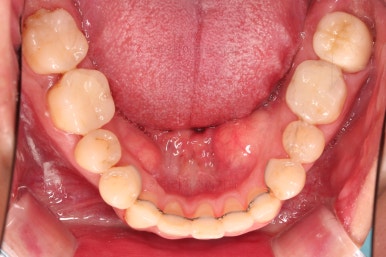

1. 초진 시 입안의 모습

부산구순구개열교정 키다리아저씨치과에 처음 내원하셨을 당시의 입안의 모습입니다.

이번 환자분도 이와 같은 일반적인 특징이 그대로 나타나 있었습니다.

양측성 구순구개열이었으므로 작은 앞니(대문니와 송곳니 사이)가 양쪽 다 결손이었고, 또 다른 이유로 아래 앞니도 1개 없는 상태였습니다.

윗니 2개, 아랫니 1개가 결손이었기 때문에 보철로 추가적으로 치아를 해 넣을지의 여부가 매우 중요했는데요

✅ 추가로 치아를 해 넣지 않고, 현재 치아만으로 교합을 맞추기로 했습니다.

결손 부위의 잇몸뼈의 상태가 썩 좋지 못하며, 대문니 2개의 상태도 장기적으로는 좋지 못할 것으로 예상되어 굳이 주위 치아에 힘을 많이 가하면서까지 공간을 확보하고 치아를 해 넣을 필요는 없다고 판단되었고요.

대신, 치아의 갯수가 위아래가 맞지 않아서 생기는 약간의 애매한 교합 부분은 감수하기로 했습니다.